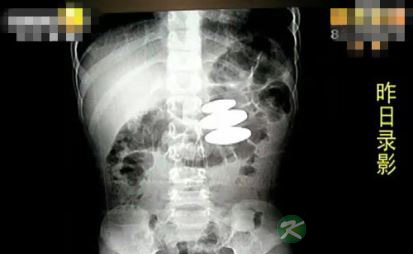

在父母的追问下军军承认,3天前觉得好玩吞了3块吸铁石,由于害怕父母责备便一直没说。得知这一情况后,军军父母立即带孩子到西安市儿童医院。经检查,军军的肚子里有3块长约2厘米、直径约1厘米的圆柱体吸铁石,3块吸铁石已吸在一起,造成军军的胃部多处溃疡。

西安市儿童医院消化科主治医生任晓侠说,吸铁石长期留在胃里,可能会造成食管穿孔等症状,所以需要通过胃镜先把3块吸铁石分开,然后再通过排泄一个一个排出来。截至发稿时,军军体内的3块吸铁石已排出了两块。任晓侠估计,最后一块最迟今天早上就会排出。记者见到排出的两块吸铁石,最大的一块长约4厘米。